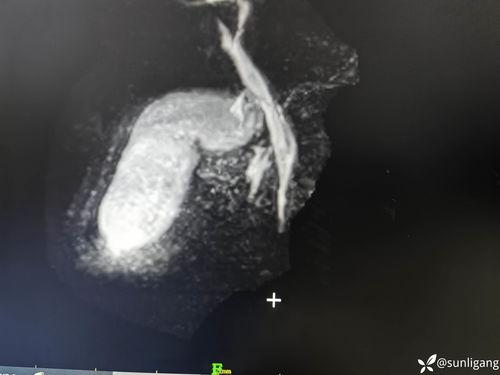

2. 手术过程:手术过程中,医生会通过小孔将手术器械伸入腹腔,切除胆囊。视频中的画面清晰,我们可以看到医生熟练的操作手法,以及手术器械在腹腔内的动态。